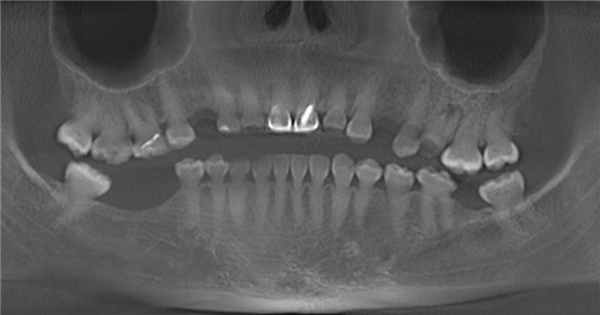

Холодовая проба отрицательная. Визуально заметная стертость окклюзионных поверхностей наблюдается только в области нижних резцов младшей сестры. Кариесом поражен только один зуб у старшей сестры. При рентгенологическом исследовании сразу же обращает на себя внимание полная облитерация полостей зубов (рис. 4).

Рис. 4. ОПТГ младшей сестры.

Только у младшей сестры в области экватора коронок нижних третьих моляров определяется просветление в виде узких горизонтальных полосок. Второе, что привлекло наше внимание на ОПГ, — низкая рентгеноконтрастность дентина, из-за чего контуры корней ряда зубов «размыты». Третья особенность — необычно малая и, наоборот, необычно большая длина корней у некоторых зубов. Четвертая особенность — из-за контраста между широкими коронками и узкими шейками зубы имеют сходство с луковицами, особенно премоляры и моляры старшей сестры. Определяется горизонтальная линия перелома в области верхушечной трети корня зуба 1.1 у старшей сестры, а также штифтовые конструкции, оси которых не совпадают с осями корней, в зубах 1.1 и 2.1 у младшей сестры. И последнее — имеются нечетко определяемые участки просветления округлой формы у верхушек корней некоторых зубов.

При определении электровозбудимости пульпы аппаратом «Дигитест» была установлена витальность пульпы ряда зубов. У старшей сестры такими оказались все верхние премоляры и третьи моляры, а также зуб 4.7; у младшей — только третьи моляры и зуб 1.4. Следует отметить, что витальным оказался один из зубов с очагом просветления на рентгенограмме.